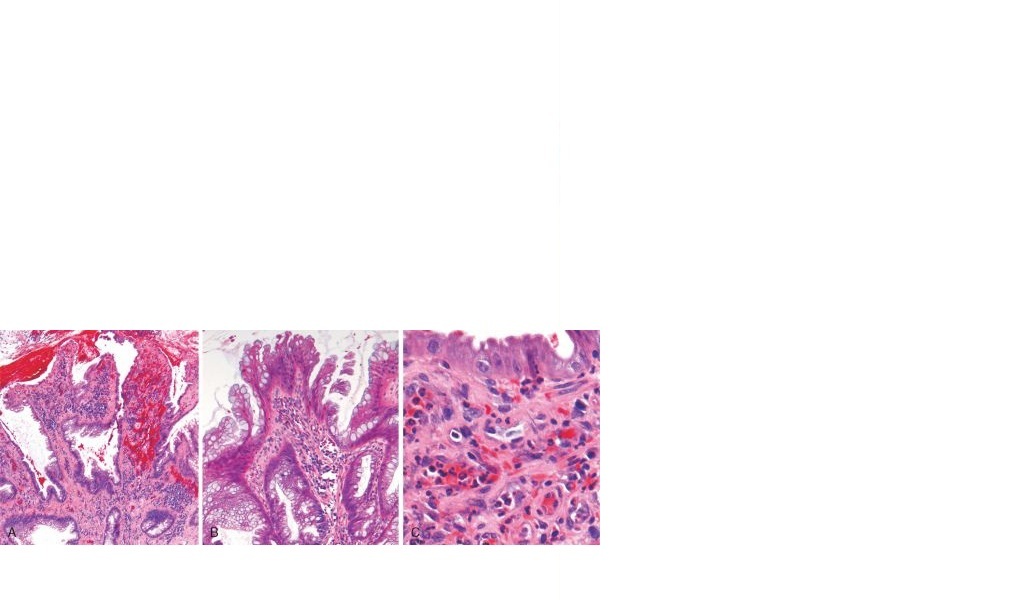

Thus, the distinctive histologic features are

those of a typical inflammatory polyp with superimposed mucosal prolapse and include lamina

propria fibromuscular hyperplasia, mixed inflammatory infiltrates, erosion, and epithelial

hyperplasia ( Fig. 17-41 ).

FIGURE 17-41 Solitary rectal ulcer syndrome.